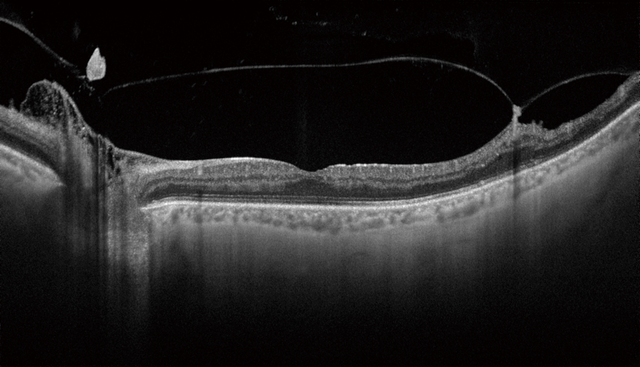

• Vitreomacular Traction Case

• Vitreomacular traction case red-free

• Vitreomacular traction case B-scan

The high penetration of the Swept Source light can easily and clearly visualize deep layers in the eye, such as choroid and sclera. A further benefit of Swept Source is that it can clearly visualize both the vitreous and choroid in a single scan, that are uniformly clear and noise-free. This eliminates the need for time consuming vitreous/choroidal combination scans.

In one single image the vitreous & choroid are revealed in a crystal clear way. The Topcon DRI OCT Triton enhances visualization of outer retinal structures and deep pathologies. The Topcon DRI OCT Triton automatically detects 7 boundaries including the chorio-scleral interface. The 12mm B-scan covers both the macular area and the optic disc.